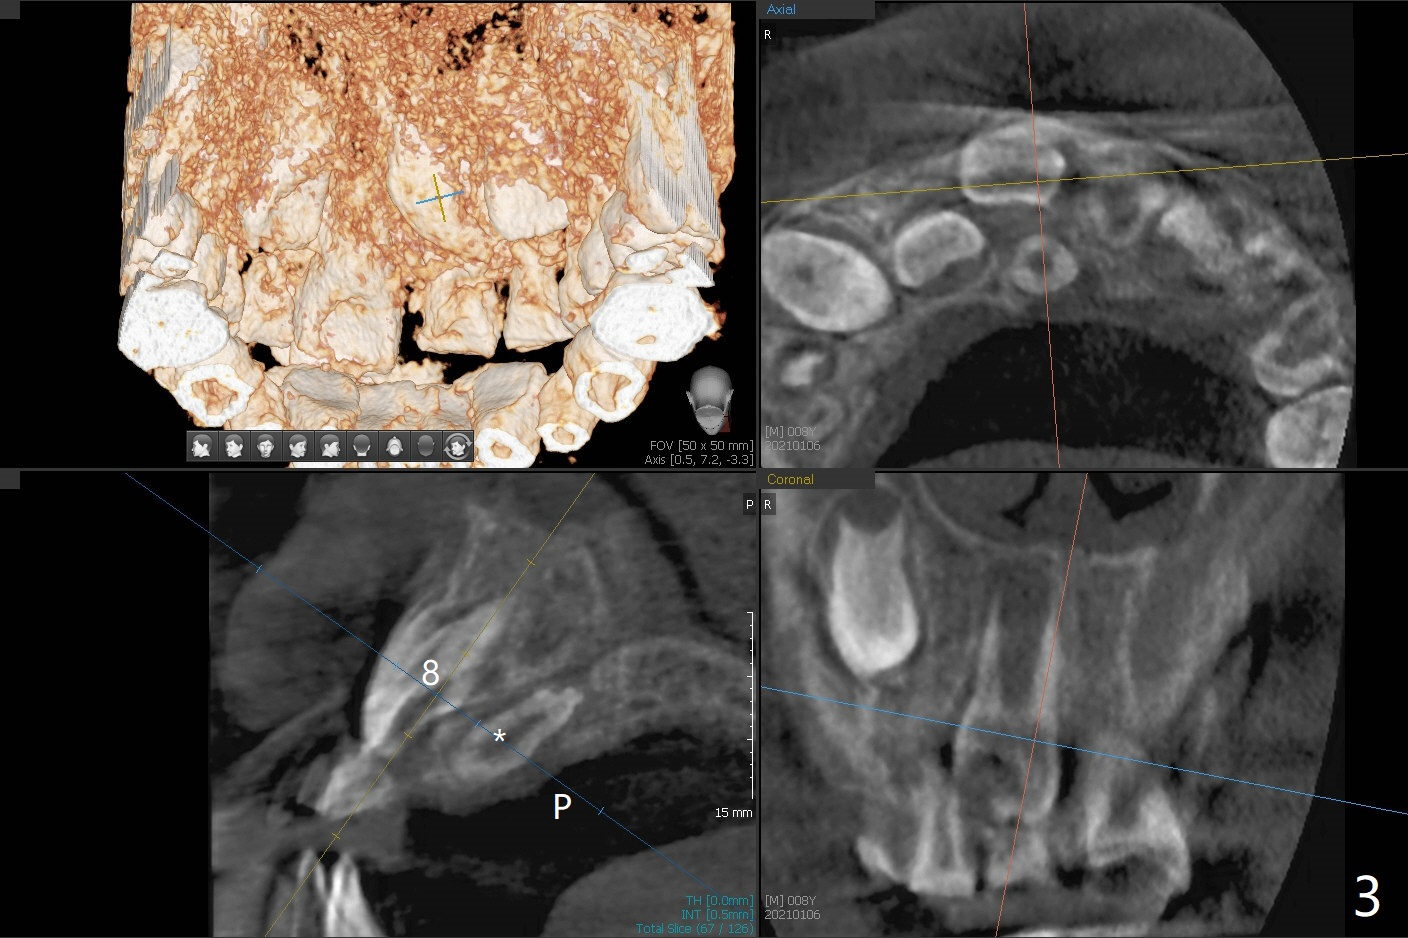

8岁男,右上乳中切牙滞留(图一,二:E),全景片,根尖片显示多生牙(图一,二:*),CT表明它位于腭侧(图三:P)。病人将今天(八岁八个月)回来拔除,腭侧牙龈缘切口应该容易暴露。